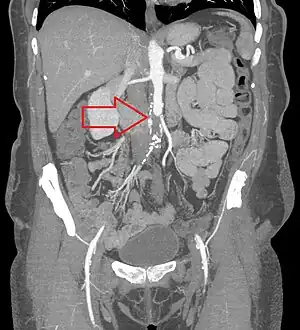

![]() | |

| CT angiogram showing a complete blockage or the aorta (red arrow) with the lower limbs supplied by collaterals | |